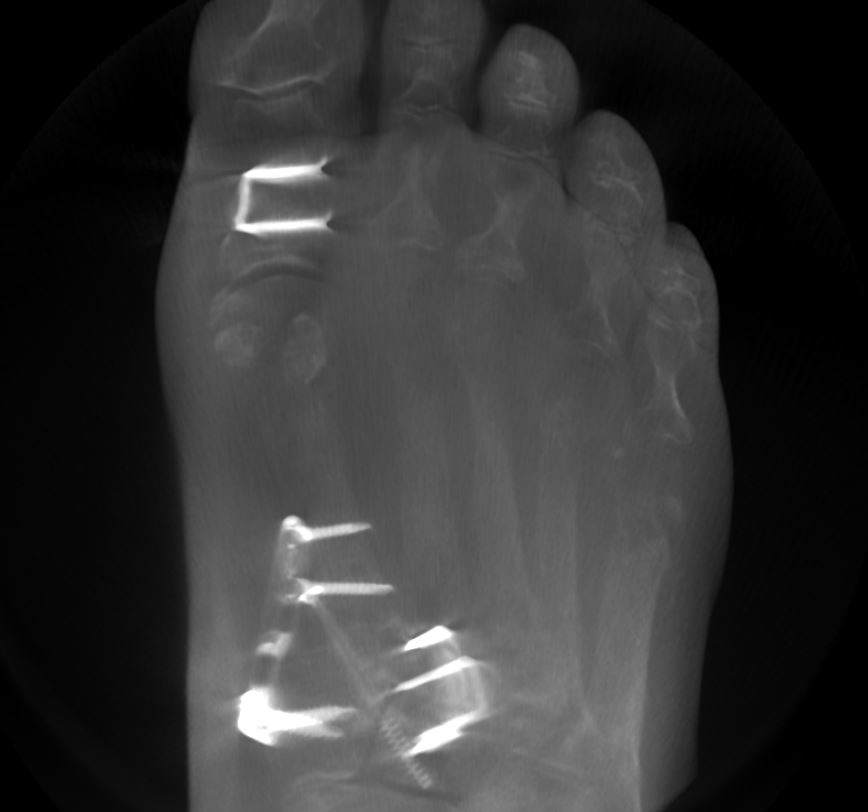

TMT 1+2 Arthrodese bei Hallux Valgus OP in Berlin